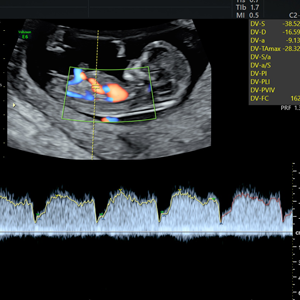

- Pionero en México en ofrecer diagnóstico por ultrasonido dentro del consultorio, así como en incorporar tecnología 3D y Doppler.